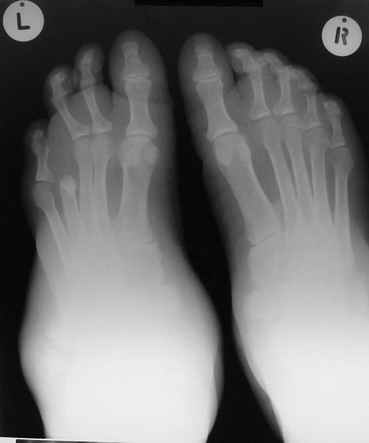

Остеосклероз при этом заболевании захватывает не всю кость по окружности, а простирается слегка волнистой

полосой вдоль длинной оси конечности (рис. 223, К), переходя через линию суставов на другие кости. Таким образом,

может оказаться пораженной целая верхняя или нижняя конечность или больший или меньший ее периферический участок,

например, часть лопатки, полуцилиндр плечевой кости, часть цилиндра лучевой кости и скелет II пальца вместе с

лежащими по этой оси участками запястных костей или же часть - медиальная или латеральная - бедренной,

болынеберцовой кости с продолжением и расширением процесса на предплюсневые и плюсневые кости и соответствующие

по длиннику фаланги одного или нескольких, но никогда не всех пальцев. Описавшие эту болезнь в 1922 г. Жоани

(Joanny) и Лери (Leri) сравнивают остеосклеротические полосы с картиной, напоминающей стекающий со свечи и

застывающий стеарин или воск, отсюда и название "мелореостоз" - "стекающая вдоль конечности кость".

Отдельные случаи мелореостоза отличаются друг от друга по степени и форме склеротических участков; каждый случай

представляет свои неповторяемые особенности. В более тяжелых случаях поражения нижней конечности захвачена и

соответствующая половина таза, при локализации в верхней конечности - часть лопатки. Из парных костей поражается,

как правило, только одна: это большеберцовая или малоберцовая кость, лучевая или локтевая кость, но никогда не